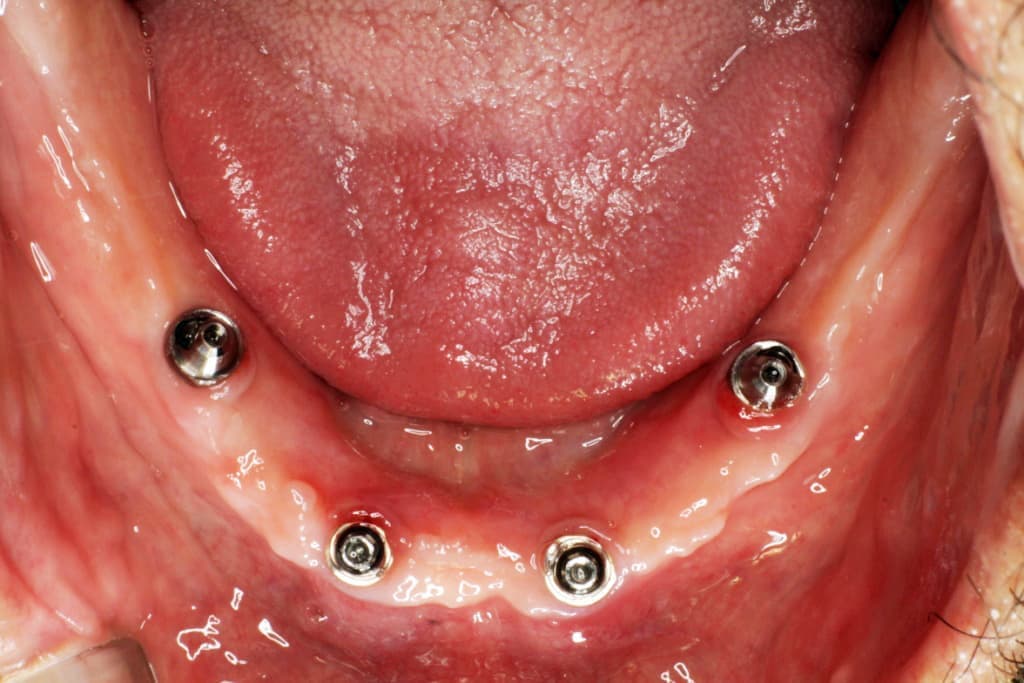

インプラントとは、顎の骨に人工歯根となる金属を埋め込み、その金属を土台にして、天然の歯と同じような人工の歯を取り付ける治療方法です。

埋め込む金属に生体との親和性が高いチタンが使われる事が多く、チタンは長年の臨床研究でインプラントの素材として最も安全であり、また顎の骨としっかり結合することが確認されています。

天然歯のような見栄えだけでなく、これまでの入れ歯やブリッジでは満足することが難しかった「食べる・話す」という機能も回復できます。

インプラントは周りの歯を傷つけず、残った歯への影響が少ないため、自分の歯を多く残せます。

また顎の骨がやせるのを防げる効果もあります。

食べ物のカスが挟まったり、留め金が見えるといったこともないので、衛生面や見た目からも、天然歯自分の歯と同じようにきれいで美しい状態を保てます。